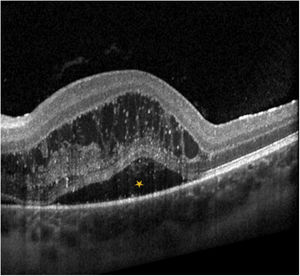

A patient aged 13 years presented with fever, unilateral colour discrimination deficits and impaired vision. The findings of blood tests and the head CT were normal. The fundoscopic examination revealed oedema in the optic disc and peripapillary retina (Fig. 1) and the optic coherence tomography scan evinced macular oedema (Fig. 2), findings compatible con neuroretinitis. The diagnosis was confirmed by serology (positive for Bartonella henselae).

Neuroretinitis secondary to B. henselae infection is rare. Its characteristic features are unilateral loss of visual acuity and visualization of optic disc oedema and exudates around the macula (macular star) in the fundoscopic examination.1–3 The macular star usually develops 1–4 weeks from onset and persists for several months (Fig. 3).2 Treatment consists of prolonged dual therapy (doxycycline and rifampicin). The use of steroid therapy remains controversial, although there is evidence suggesting that it may improve fundoscopic abnormality and visual acuity outcomes.1,3